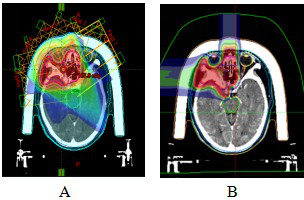

图7 眼眶ACC患者离子治疗剂量分布图

Figure 7 Ion therapy dose distribution in orbital ACC patients

Note: Figure 7A: One course CIRT dose distribution. Figure 7B: Two course CIRT dose distribution

图8 眼眶ACC患者VMAT计划及碳离子计划剂量分布图

Figure 8 VMAT plan and carbon ion plan dose distribution in orbital ACC patients

Note: Figure 8A: VMAT plan dose distribution n orbital ACC patients. Figure 8B: Carbon ion plan dose distribution n orbital ACC patients.